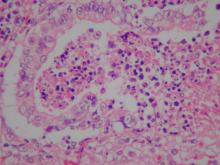

扁桃腺:可見明顯之凝固性壞死灶,壞死灶以細胞核之濃縮、破裂為主徵,壞死區周

圍上皮細胞可見明顯之嗜酸性核內包涵體(圖3)。2.

淋巴結:可見明顯之凝固性壞死灶,壞死灶以細胞核之濃縮、破裂為主徵。 3.

肺臟:纖維素性壞死性肺炎,可見肺水腫及凝固性壞死灶,支氣管上皮細胞可見明顯

之嗜酸性核內包涵體(圖4)。四、 實驗室檢驗: 1.